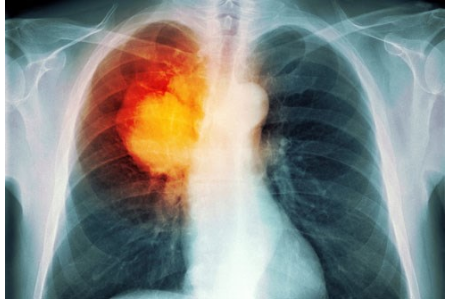

Trong hầu hết các trường hợp, khi bác sĩ nghi ngờ bệnh nhân mắc ung thư phổi với các triệu chứng điển hình như ho mãn tính hoặc thở khò khè, lúc đó, bác sĩ sẽ cho người bệnh đi chụp X-quang hoặc các xét nghiệm hình ảnh khác. Bệnh nhân cũng có thể được yêu cầu xét nghiệm đờm. Nếu một trong các xét nghiệm cho thấy xuất hiện dấu hiệu của ung thư, bước tiếp theo bác sĩ sẽ tiến hành sinh thiết phổi.

Phương pháp điều trị nhắm mục tiêu là một phương thức điều trị mới của ung thư phổi, nó có thể được sử dụng cùng với hóa trị liệu hoặc khi các phương pháp điều trị khác không hiệu quả. Phương pháp nhắm mục tiêu là nhằm chặn các mạch máu tới nuôi dưỡng tế bào ung thư ở khối u. Nó có thể giúp bệnh nhân ung thư phổi sống lâu hơn. Phương pháp điều trị nhắm mục tiêu có thể làm gián đoạn các tín hiệu chịu trách nhiệm nhân lên trong tế bào ung thư trong hình ảnh ở trên.